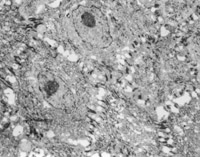

2. 電鏡觀察 受傷當(dāng)日上皮組織變性壞死,可見(jiàn)單核細(xì)胞核偏移、固縮,并有吞噬現(xiàn)象(圖5-3-12)。

5-3-12 燒傷當(dāng)日,單核細(xì)胞核偏移,固縮,并有吞噬現(xiàn)象  TE×8000